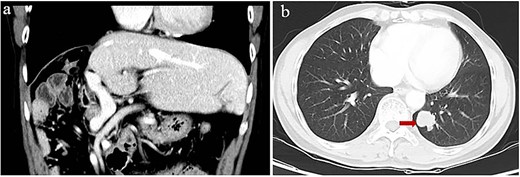

At 24 months after his admission with hepatic occupation, contrast-enhanced computed tomography detected intrahepatic recurrence, which was confirmed by magnetic resonance imaging. The patient was admitted again and given two cycles of transarterial chemoembolization (TACE), which achieved a partial response (PR) based on the Response Evaluation Criteria for Solid Tumors [18] (Fig. 2a and b). At 16 weeks after his second admission, the patient underwent right hemihepatectomy. Baseline variables before surgery are described in Supplementary Table 1. The surgery proceeded smoothly, and the patient recovered well. Postoperative histopathology revealed necrosis in more than 90% of the tumor, whereas no nodular cirrhosis, satellite nodules, or tumor emboli were observed. Instead, necrotic and proliferative fibrous tissue with multinucleated giant cells was observed, with abundant infiltration by lymphocytes and focal aggregation of neutrophils (Fig. 2c and d). Surrounding liver tissue showed chronic hepatitis changes (G2S2 on the inflammation and fibrosis scale) as well as hyperplasia of the small bile duct.

Intrahepatic recurrence and response to TACE. (a, b) Contrast-enhanced computed tomography in the (a) arterial phase or (b) venous phase after two cycles of TACE, showing PR of the recurrent tumor liver. (c, d) Histopathology of recurrent tumor after TACE at magnifications of (c) 40× or (d) 100×, showing necrosis of more than 90% of the tumor, proliferative fibrous tissue (leftward arrows), blue embolic agent in vasculature (rightward arrows), multinucleated giant cells, and abundant infiltration by lymphocytes (downward arrow).